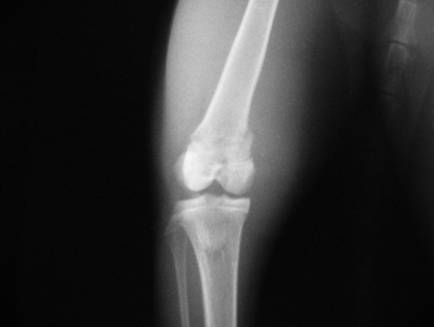

Как долго заживает перелом

В зависимости от того, какая кость была повреждена, время восстановления полной анатомической целостности кости варьируется. Считается, что трубчатые кости, в силу специфики своего строения, заживают быстрее. Однако, размер играет важную роль. Так, например, на полное заживление лучевой кости уходит приблизительно 1 месяц. Большая берцовая восстанавливается в течение 2 -2,5 месяцев. На малую берцовую кость уходит немногим меньше времени – 1,5 – 2 месяца. Восстановление тазобедренных костей занимает более длительное время – не менее 3 месяцев. На временной фактор также влияют другие особенности:

Оглавление темы «Переломы костей. Рентгенологические признаки переломов»:1. Дистальная и проксимальная эктромелии. Патология пальцев и конечностей2. Нарушение количества пальцев. Расщепление кисти и синдактилия3. Симфалангия и патология стопы. Множественные пороки скелета4. Травмы скелета. Переломы костей скелета5. Переломы трубчатых костей. Возрастные особенности переломов6. Вторичное заживление костей. Осложненные переломы7. Огнестрельные переломы. Патологические переломы8. Патологическое заживление переломов. Ложный сустав — псевдоартроз9. Переломы пояса верхней конечности. Переломы костей верхних конечностей10. Переломы костей таза и тазобедренного сустава. Переломы бедра, костей коленного сустава